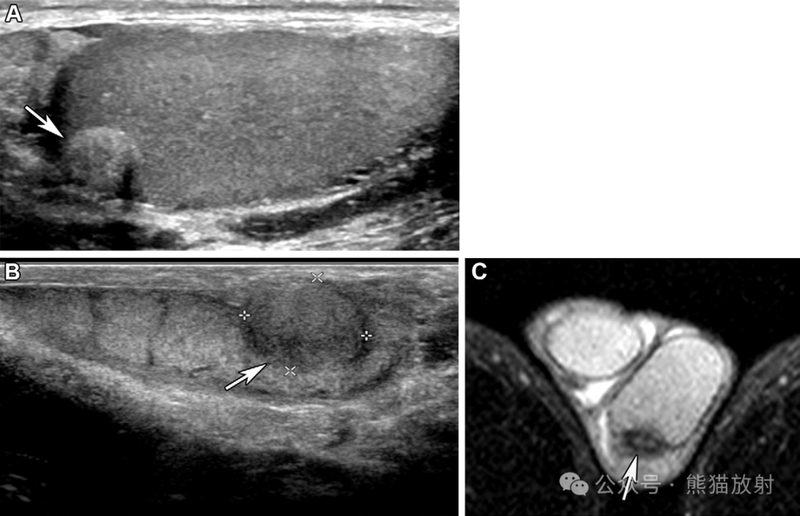

57岁男性,睾丸鞘膜间皮瘤。阴囊的灰度 (A) 和彩色多普勒 (B) US图像显示睾丸旁不均质回声病变(A箭),血流增加(B箭)。

腺瘤样肿瘤两例。(A) 61岁男性,阴囊偶发肿块。阴囊的纵向灰度超声图像显示附着在睾丸白膜上的有回声的病变(箭), 延伸至邻近的睾丸实质。(B,C) 29岁男性,灰度超声(B) 和T2WI(C) 图像显示左侧附睾边界清楚的等回声结节,T2低信号病变(箭头)。